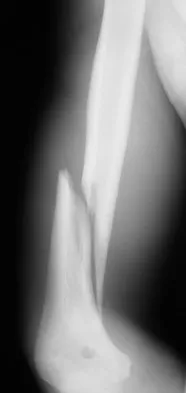

A 35-year-old man sustained the closed injury shown in Figure 52 in his dominant extremity. Neurologic function is normal. Treatment should consist of